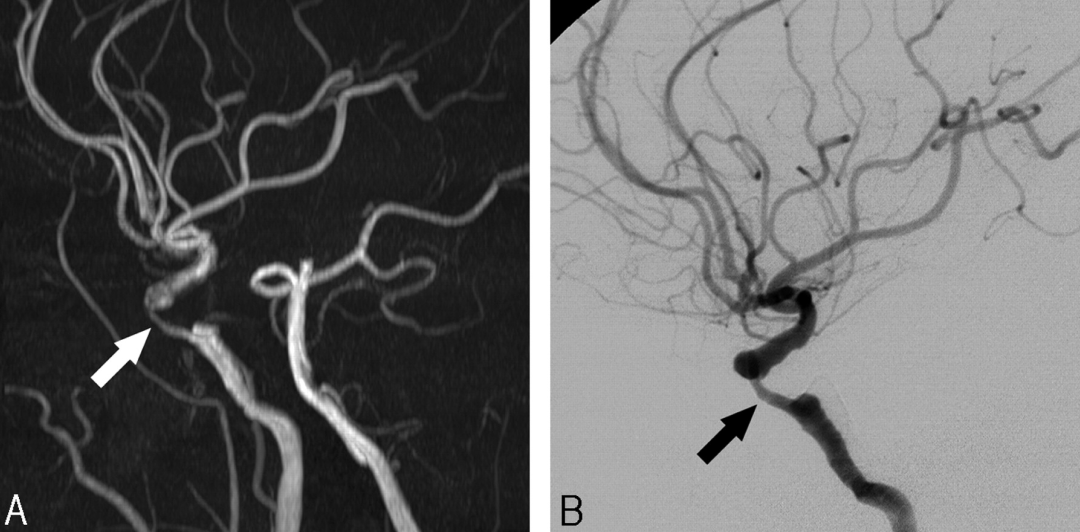

CT scans provide high-resolution images of the brain, making it easier to detect blood vessel narrowing. However, due to the complexity of brain structures, advanced segmentation and annotation techniques are needed for precise diagnosis.

Segmentation divides CT images into regions of interest, isolating blood vessels and detecting narrowed sections caused by plaque buildup.

Standard CT scans can be difficult to interpret, especially when dealing with intricate brain structures. AI-based segmentation enhances image clarity, allowing doctors to easily distinguish between normal and narrowed blood vessels.

Segmentation helps measure the exact degree of narrowing in blood vessels, allowing doctors to determine whether a patient needs: